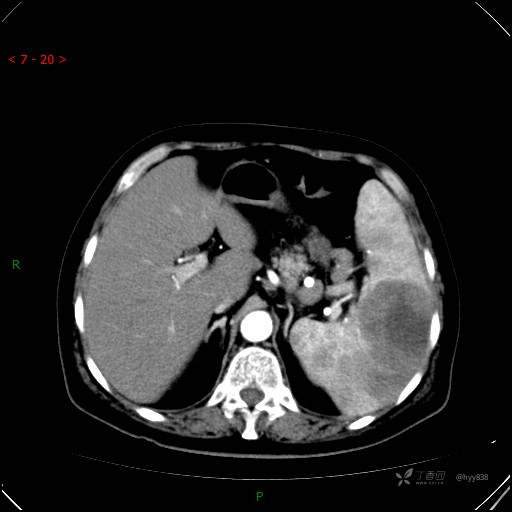

动脉期